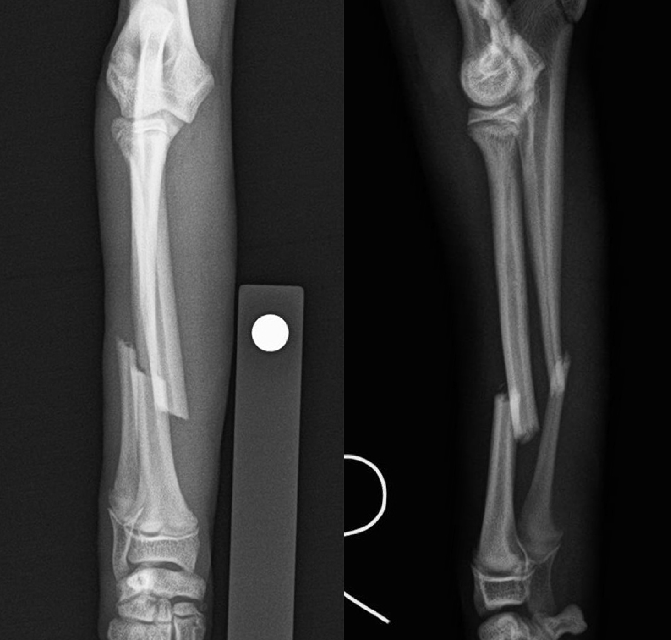

骨折

小型犬の前肢骨折(橈尺骨骨折)は転倒や落下で簡単に骨折します。

ほとんどがプレートとスクリュー固定にて完治できますからできるだけ早期に手術を行います。

術後は関節の拘縮や筋肉の萎縮を予防するため適度な運動とリハビリが重要です。

骨折した肢を負重することで早期に骨癒合が促されます。

骨癒合が得られればスクリューを外す手術を行います。

【術前】橈尺骨遠位端プレート整復固定 -

【術後】橈尺骨遠位端プレート整復固